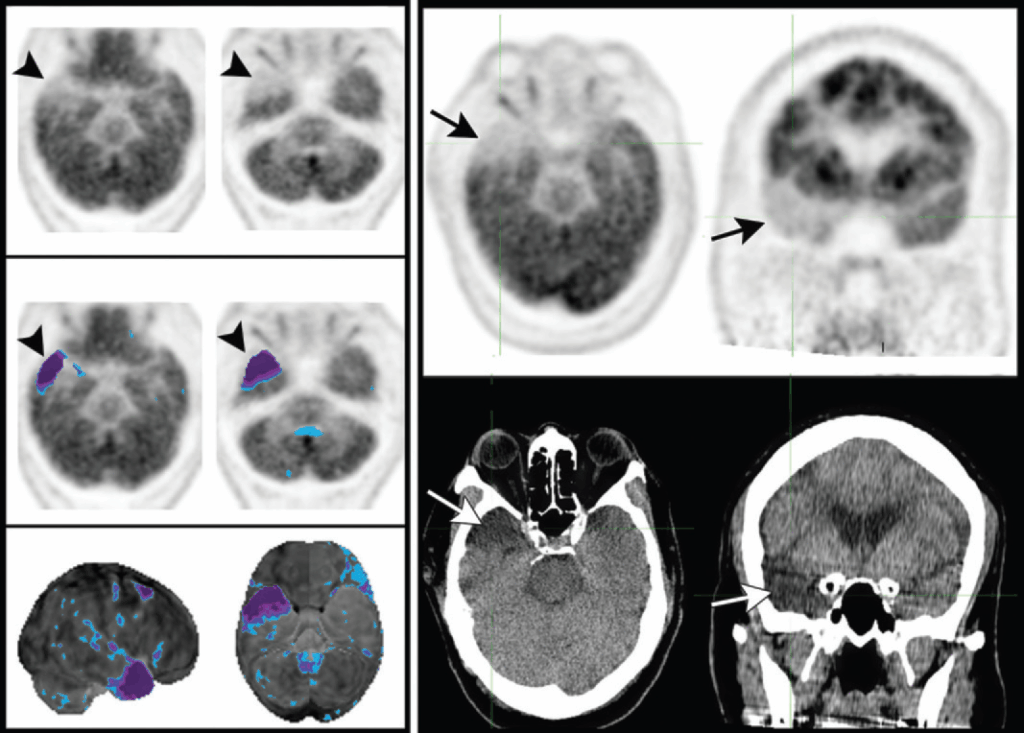

Sindromi Neurodegenerative Rare

- Degenerazione Corticobasale: questa patologia è caratterizzata da una marcata asimmetria dell’ipometabolismo, che coinvolge la corteccia sensomotoria e, omolateralmente, i gangli della base o il talamo.

- Atrofia Cerebrale Posteriore (PCA): considerata una variante atipica dell’AD, la PCA si presenta con un pattern di ipometabolismo parietotemporale e occipitale posteriore, ma con il coinvolgimento aggiuntivo delle cortecce associative visive laterali, che spiega i deficit visivi complessi tipici di questa sindrome.

È imperativo procedere a un’ispezione sistematica delle immagini anatomiche (TC o RM) del paziente prima di refertare lo studio metabolico. Lesioni strutturali come tumori, cisti aracnoidee o aree di encefalomalacia post-ischemica possono causare difetti metabolici focali che possono mimare o confondere i pattern tipici delle malattie neurodegenerative. La corretta ispezione delle immagini morfologiche previene errori da falso positivo.

È necessario saper identificare e gestire i seguenti artefatti comuni:

- movimento del paziente: un disallineamento tra le immagini PET e la TC utilizzata per la correzione dell’attenuazione può creare aree di apparente ipometabolismo (artefatto da errata sottrazione, o oversubtraction artifact). Questo artefatto potrebbe non essere evidente analizzando le sole immagini PET corrette. La revisione delle immagini PET non corrette per l’attenuazione è un controllo di qualità essenziale per rilevare questo problema;

- atrofia cerebrale: una significativa riduzione del volume cerebrale, con conseguente allargamento dei solchi, può essere erroneamente interpretata dai software di mappatura statistica (SPM) come un’area di ipometabolismo corticale. È quindi cruciale correlare sempre le mappe statistiche con le immagini PET native per distinguere un vero ipometabolismo da un artefatto dovuto all’atrofia;

- artefatti da mappatura statistica (SPM): un artefatto comune si manifesta come una sottile area di “ipometabolismo” all’interfaccia tra la materia grigia e la sostanza bianca. La chiave per riconoscerlo è verificare che tale area si co-registri con la sostanza bianca e non si estenda fino alla superficie corticale, dove si trova la materia grigia.